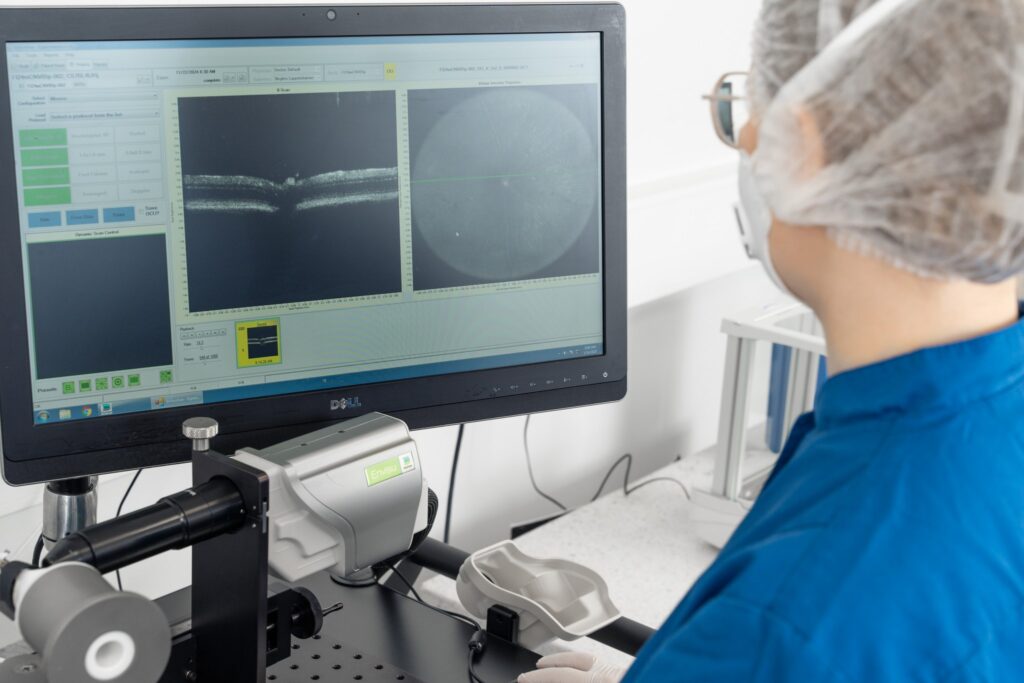

To track disease progression and evaluate treatment effects, Experimentica uses in vivo imaging and functional assessments for long-term monitoring of the STZ-induced diabetic retinopathy model. Spectral-domain optical coherence tomography (SD-OCT) captures high-resolution images of the retinal layers, allowing assessment of retinal thinning. Pattern electroretinography (pERG) evaluates retinal ganglion cell (RGC) function, while optomotor response test assesses visual acuity and contrast sensitivity.

– Retinal layer thickness measurements (SD-OCT),